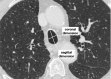

Fig. 13

HRCT demonstrates subpleural basal reticulations in a never-smoker 78-year-old man (arrows) (A). Axial image in a 67-year-old man with a diagnosis of idiopathic pulmonary fibrosis shows diffuse irregular septal thickening, traction bronchiectasis, and honeycombing (B)